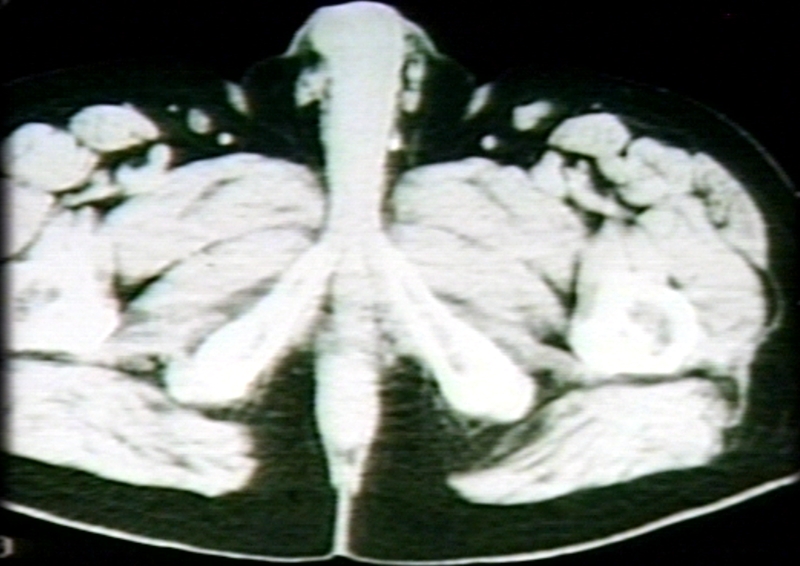

RADIOLOGY: PELVIS: PERINEUM, MALE, SCROTUM; MP-3, F6-2; INFERIOR PUBIC RAMUS (CT)